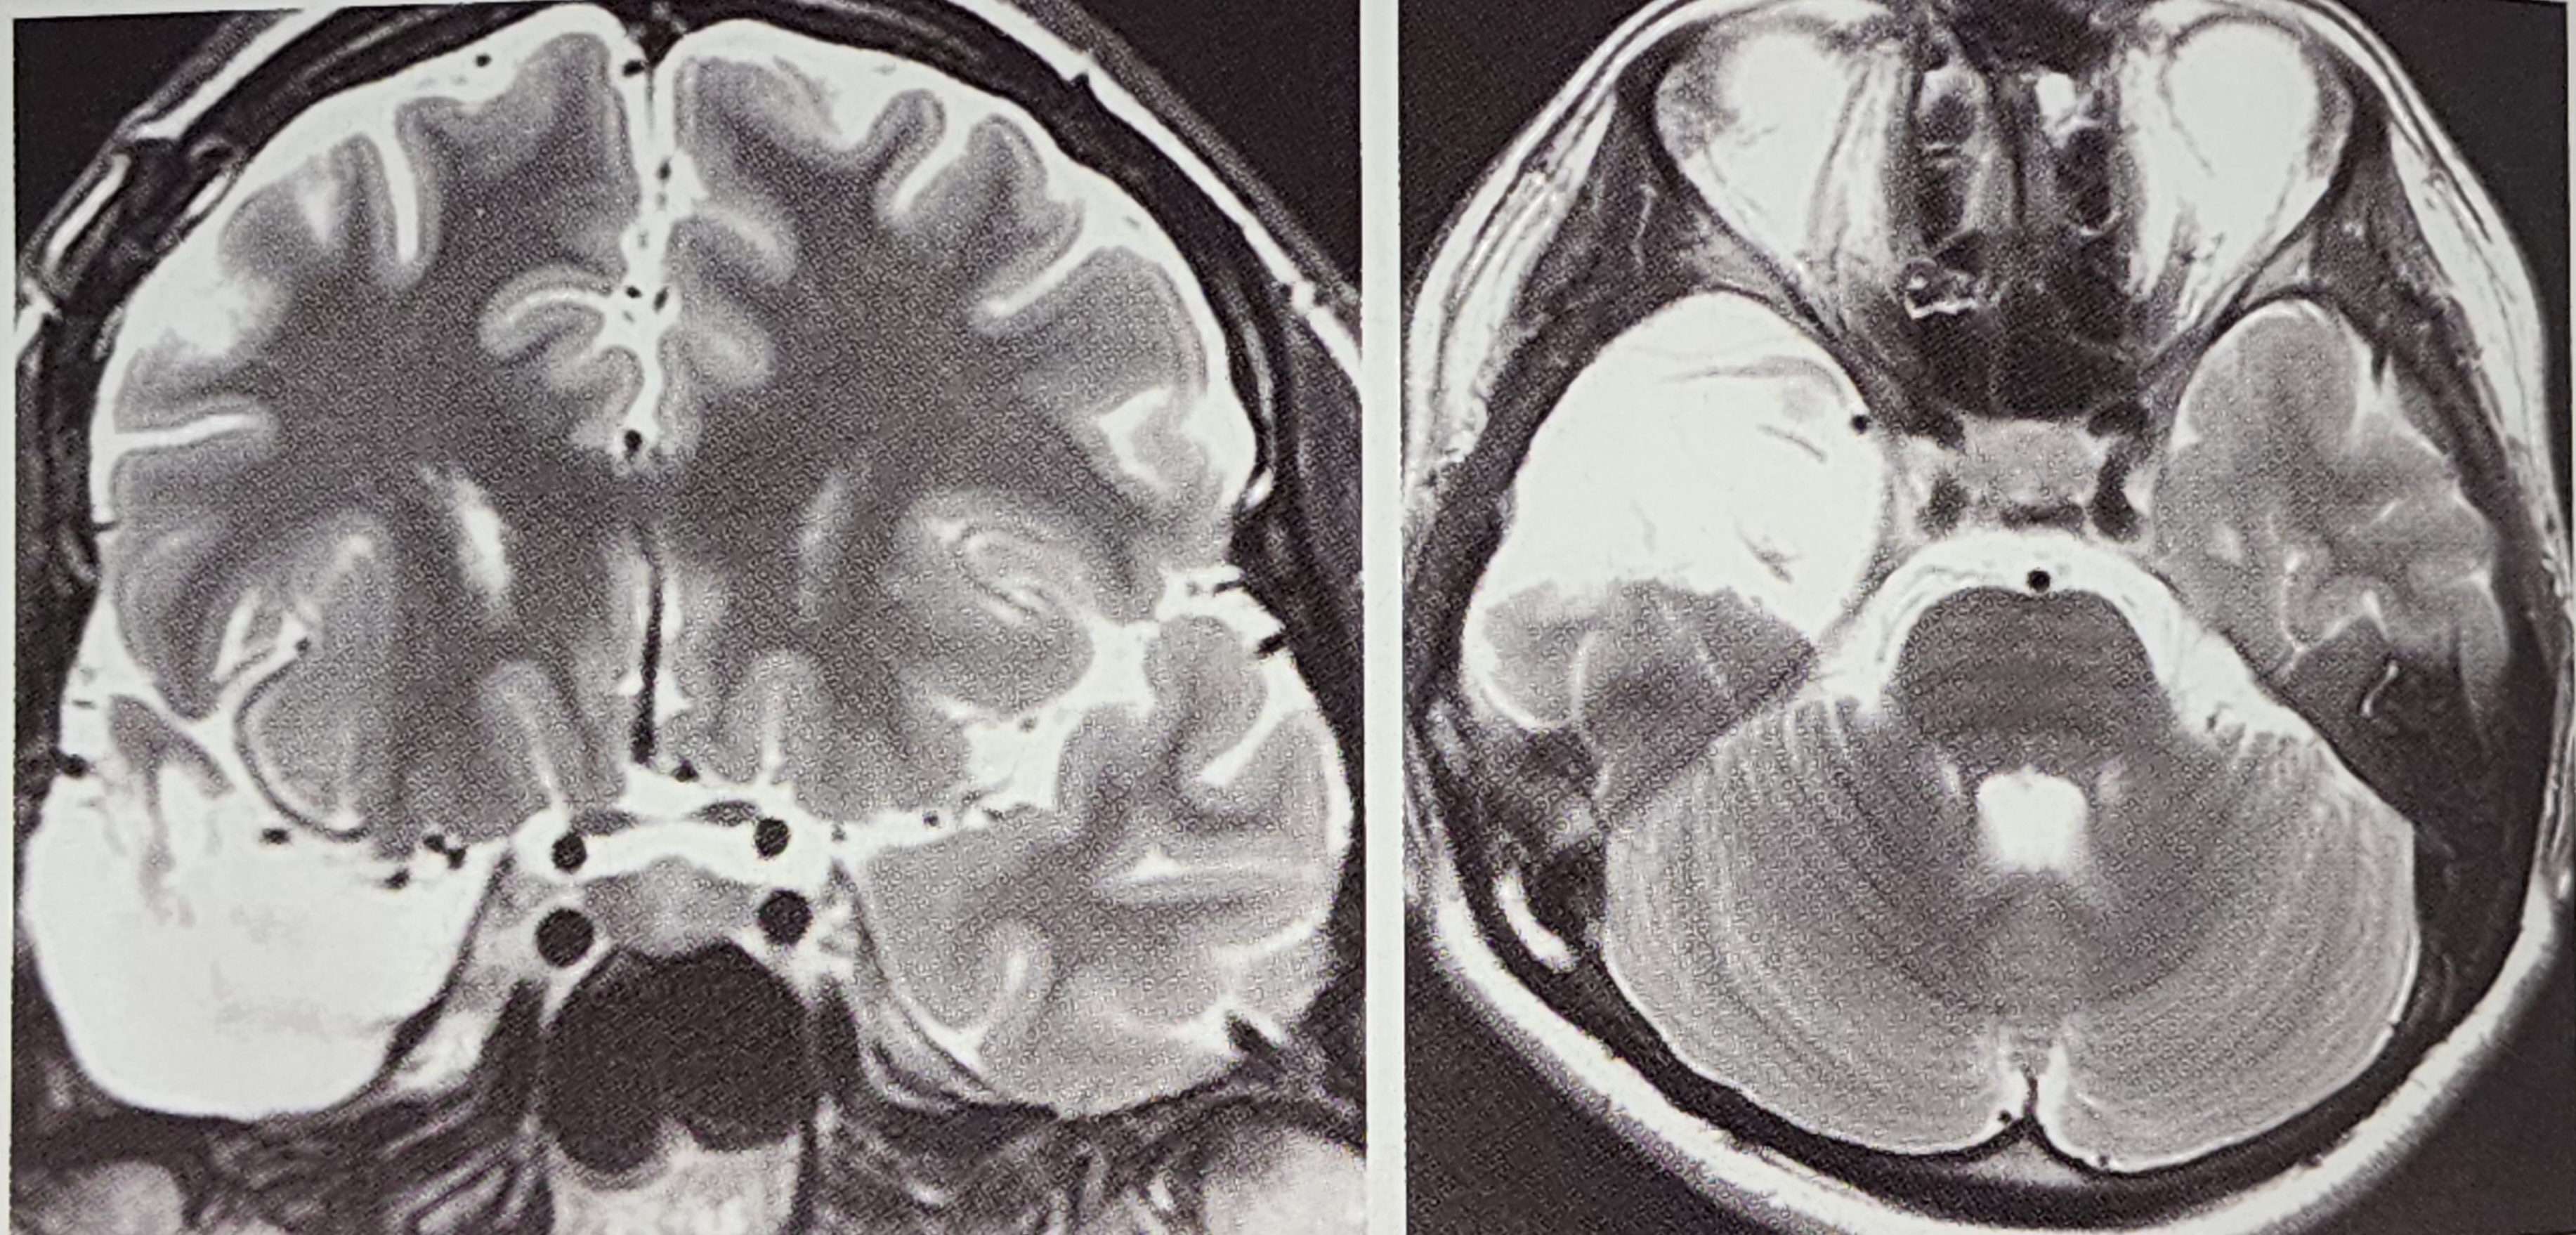

3.1 MRI(자기공명영상) 검사

MRI는 해마경화증이나 측두엽 구조 이상을 확인하는 가장 중요한 검사법이다. 특히 FLAIR(Fluid-Attenuated Inversion Recovery) 기법을 사용하여 뇌조직의 손상을 더욱 명확히 확인할 수 있다.